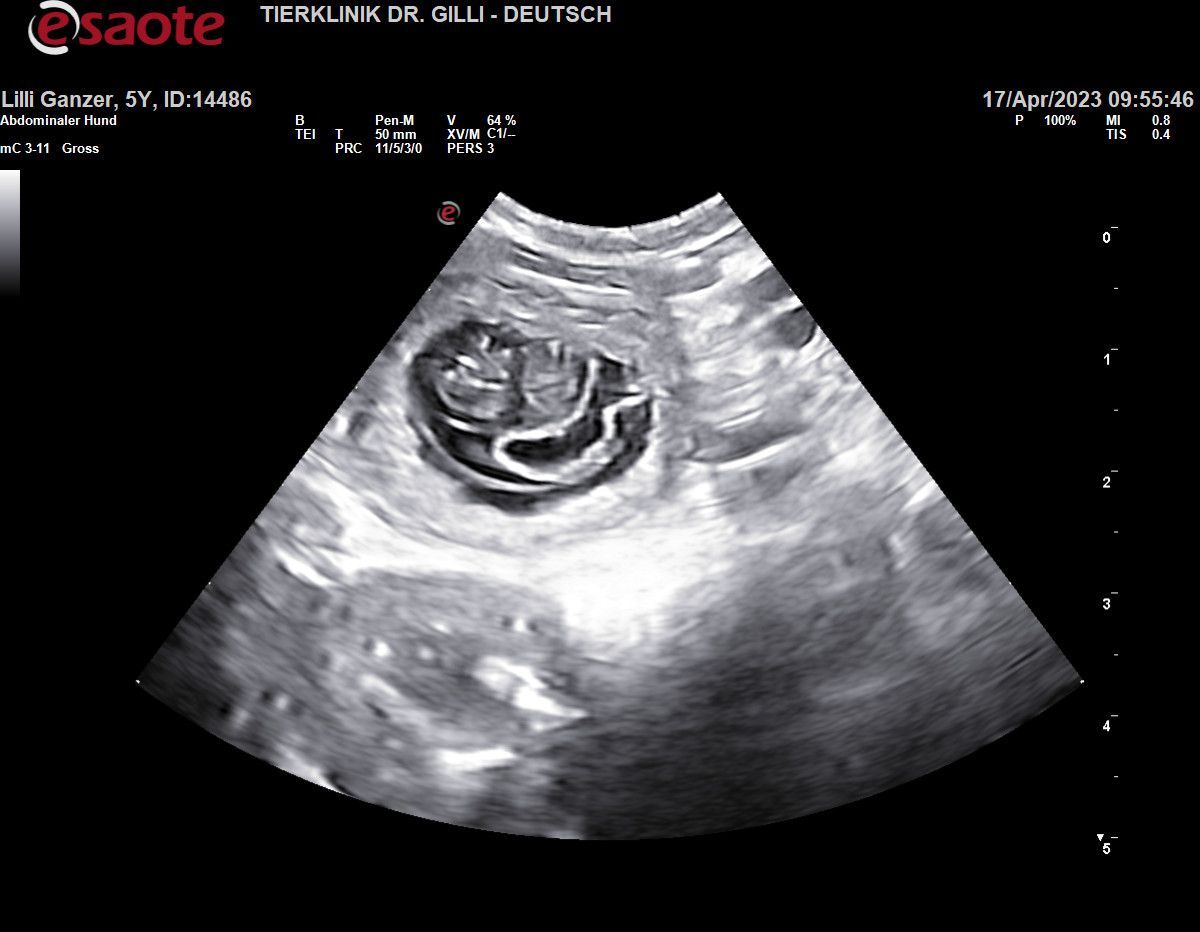

Heute Nacht, 20.05.2023, war es nun endlich soweit!!!

ab 2:50 Morgens bis 5:22 brachte unsere Lilli Fee, 5 bildhübsche Babys zur Welt!!!

Mama & den Babys geht es ausgezeichnet. es war eine Bilderbuch Geburt

es sind 3 Buben und 2 Mädchen

wir werden jeden Einzelnen, in den nächsten Tagen vorstellen